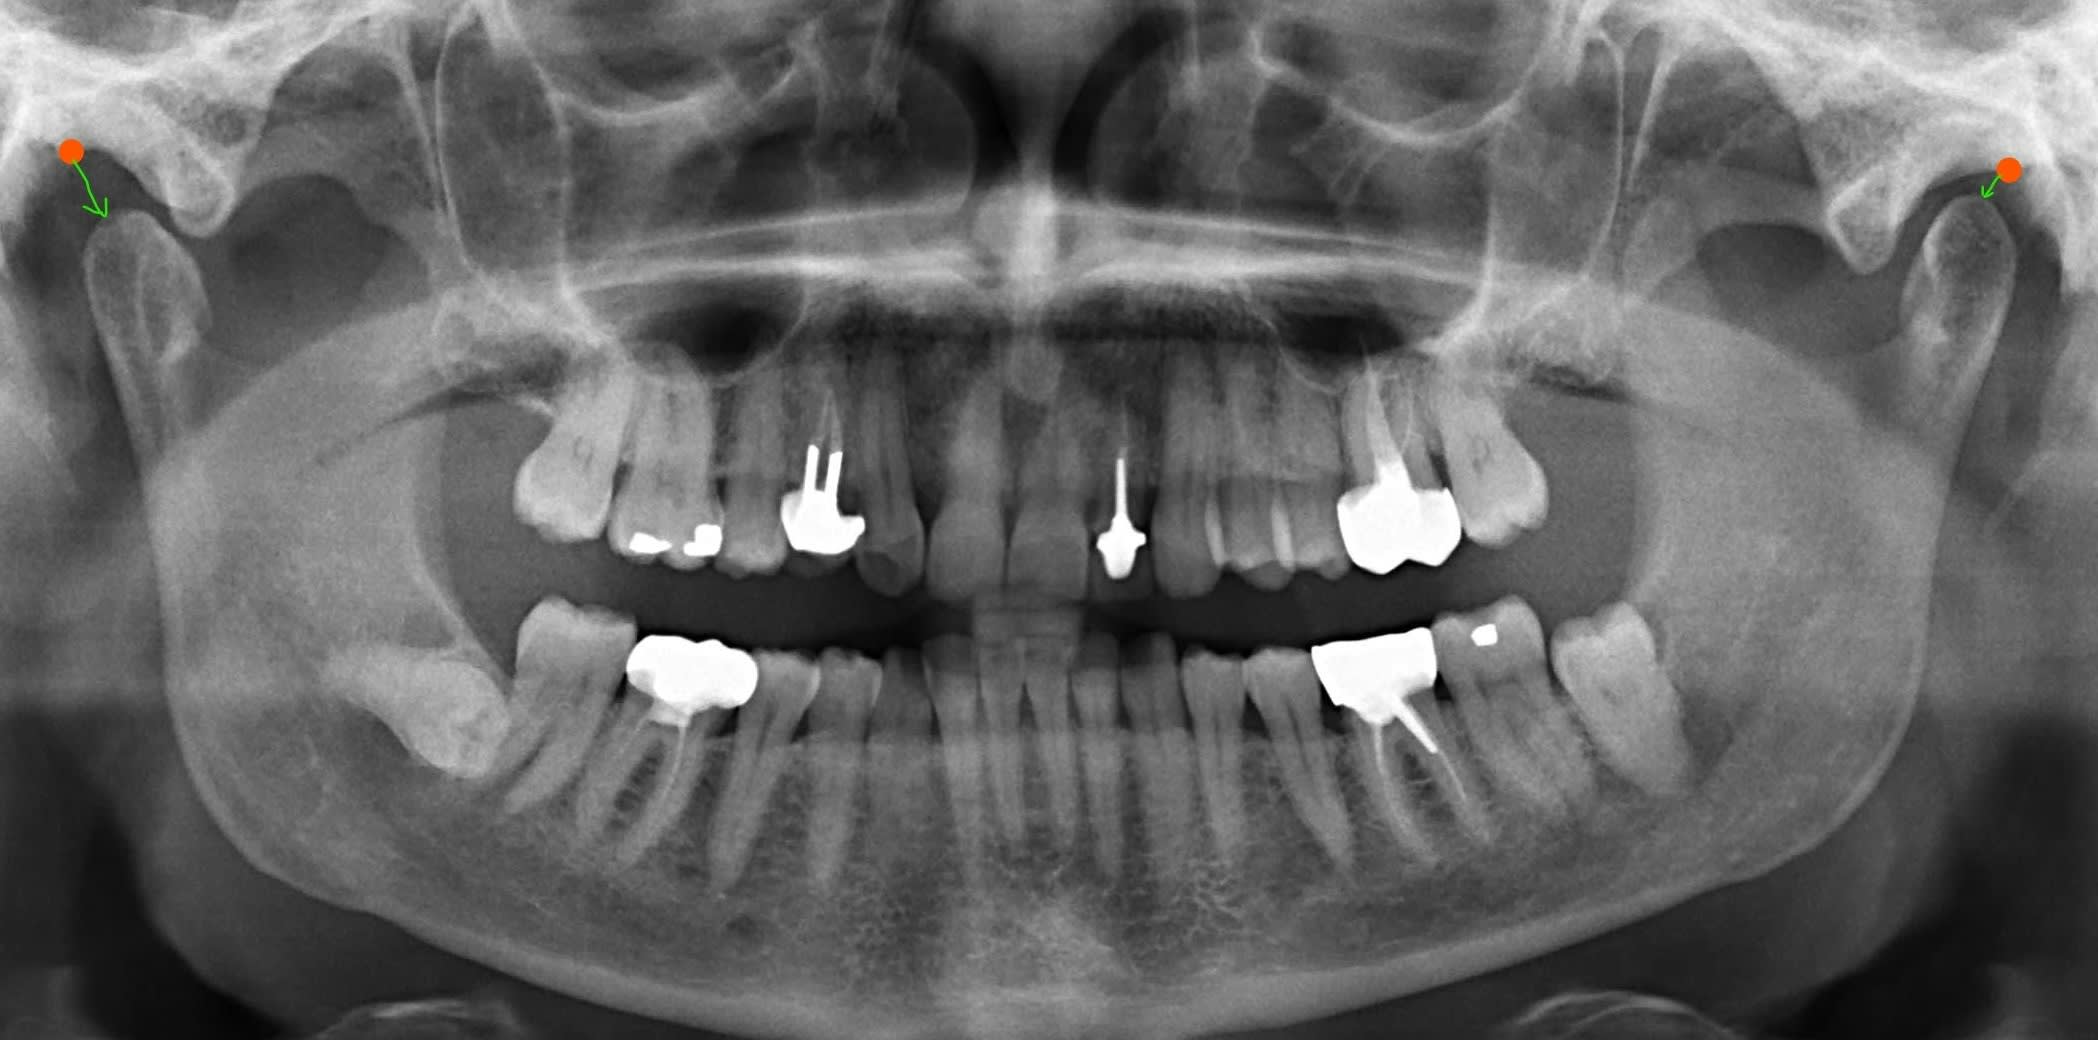

Voila la panoramique!

Sur la pano, on a plus l’impression que c’est la crête distale de la 46 qui est absente.

oui on dirait . peut etre tout simplement une cc pipée en sous occ .

le plus surprenant , c est que malgré le chaos que l on a prédit du au visuel des usures , , l os ne semble pas avoir morflé . l endo n est pas top et pourtant il n y a pas de granulome non plus ... pour ça que je pensais à la sous occ initiale

Tu noteras la facette d'usure monstrueuse en mésial de 47, j'étais persuadé qu'il y aurait une restauration à la radio, vu la différence en comparaison des sillons conservés en distal.